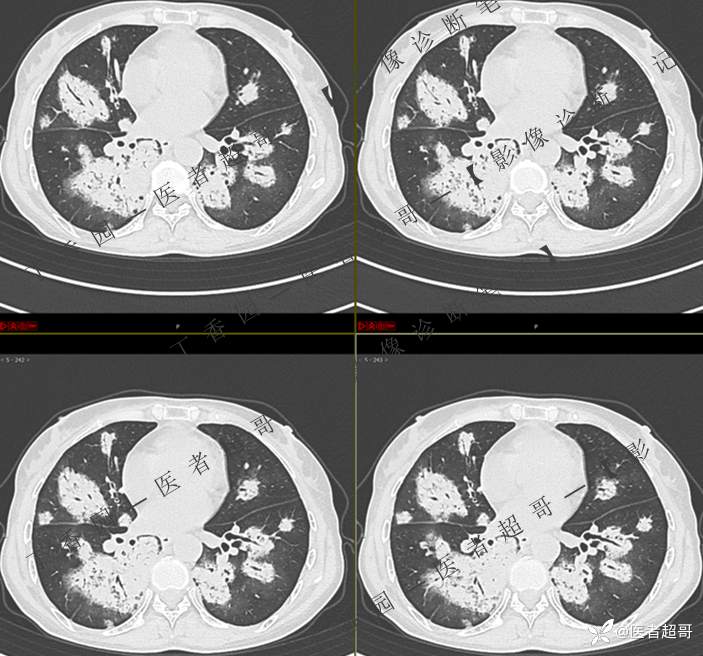

2402胸部影像病例︱持续追踪的一个患者,时间轴较长,闭卷分析,请畅所欲言~~~

女性,57岁

主 诉:发热伴咳嗽咳痰1周

现病史:1周前患者无明显原因及诱因出现发热,最高体温39.0℃,伴咳嗽后胸痛及全身酸痛,伴咳嗽,流涕,伴痰中带有血丝,鲜红色,无背板、头晕、头痛、恶心、呕吐,患者未就诊于医院,行“川贝止咳”,未服用抗生素,后于1天前就诊于我院门诊,现为行进一步治疗,入住我科,患者自起病以来,精神饮食可,大小便正常。